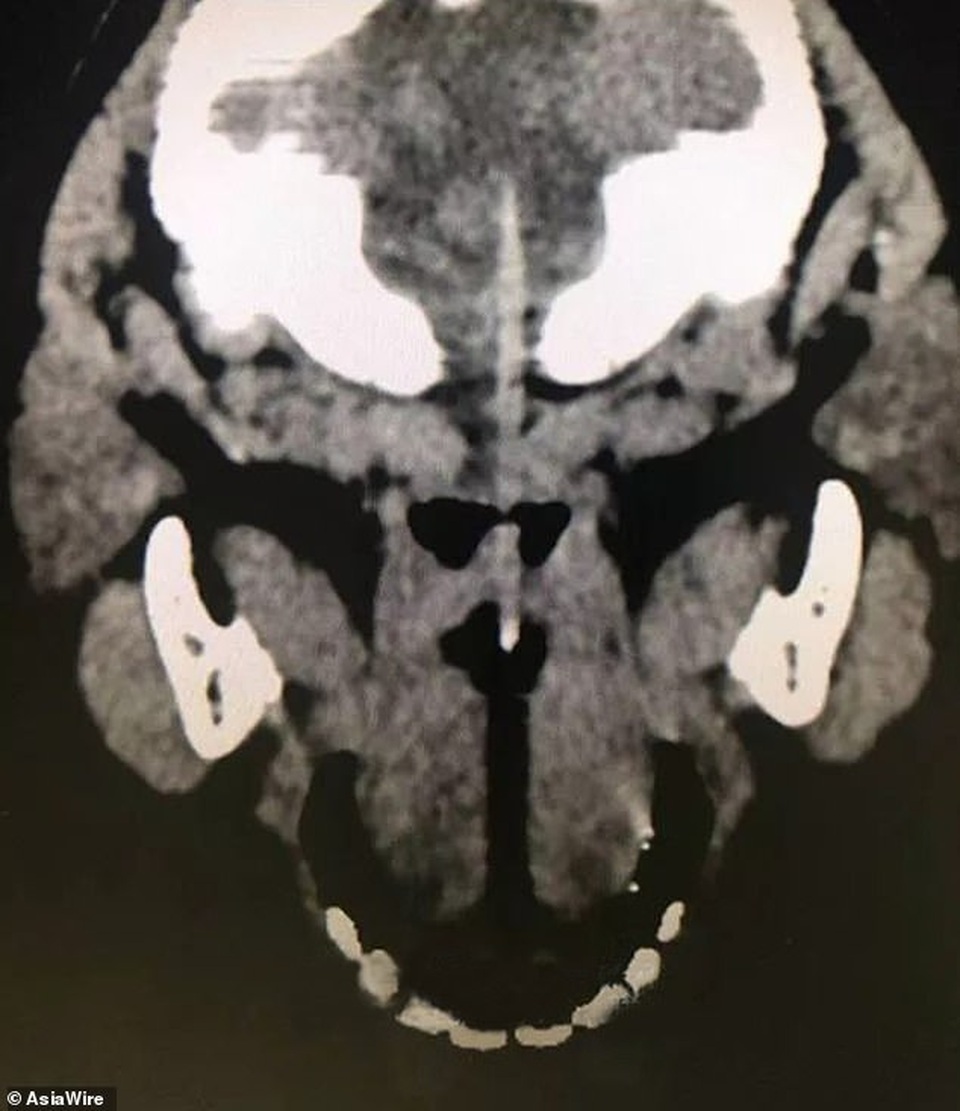

Cậu bé 3 tuổi sống tại tỉnh Chiết Giang (Trung Quốc) đã ngay lập tức được đưa tới Bệnh viện Nhi Đại học Dược Chiết Giang sau khi tai nạn xảy ra. Que xiên bằng tre dài 10cm đã đâm qua miệng em và xuyên vào hộp sọ. Kết quả chụp CT cho thấy que xiên đã đâm vào thân não của cậu bé.

Hình chụp cho thấy chiếc que đâm vào não cậu bé.